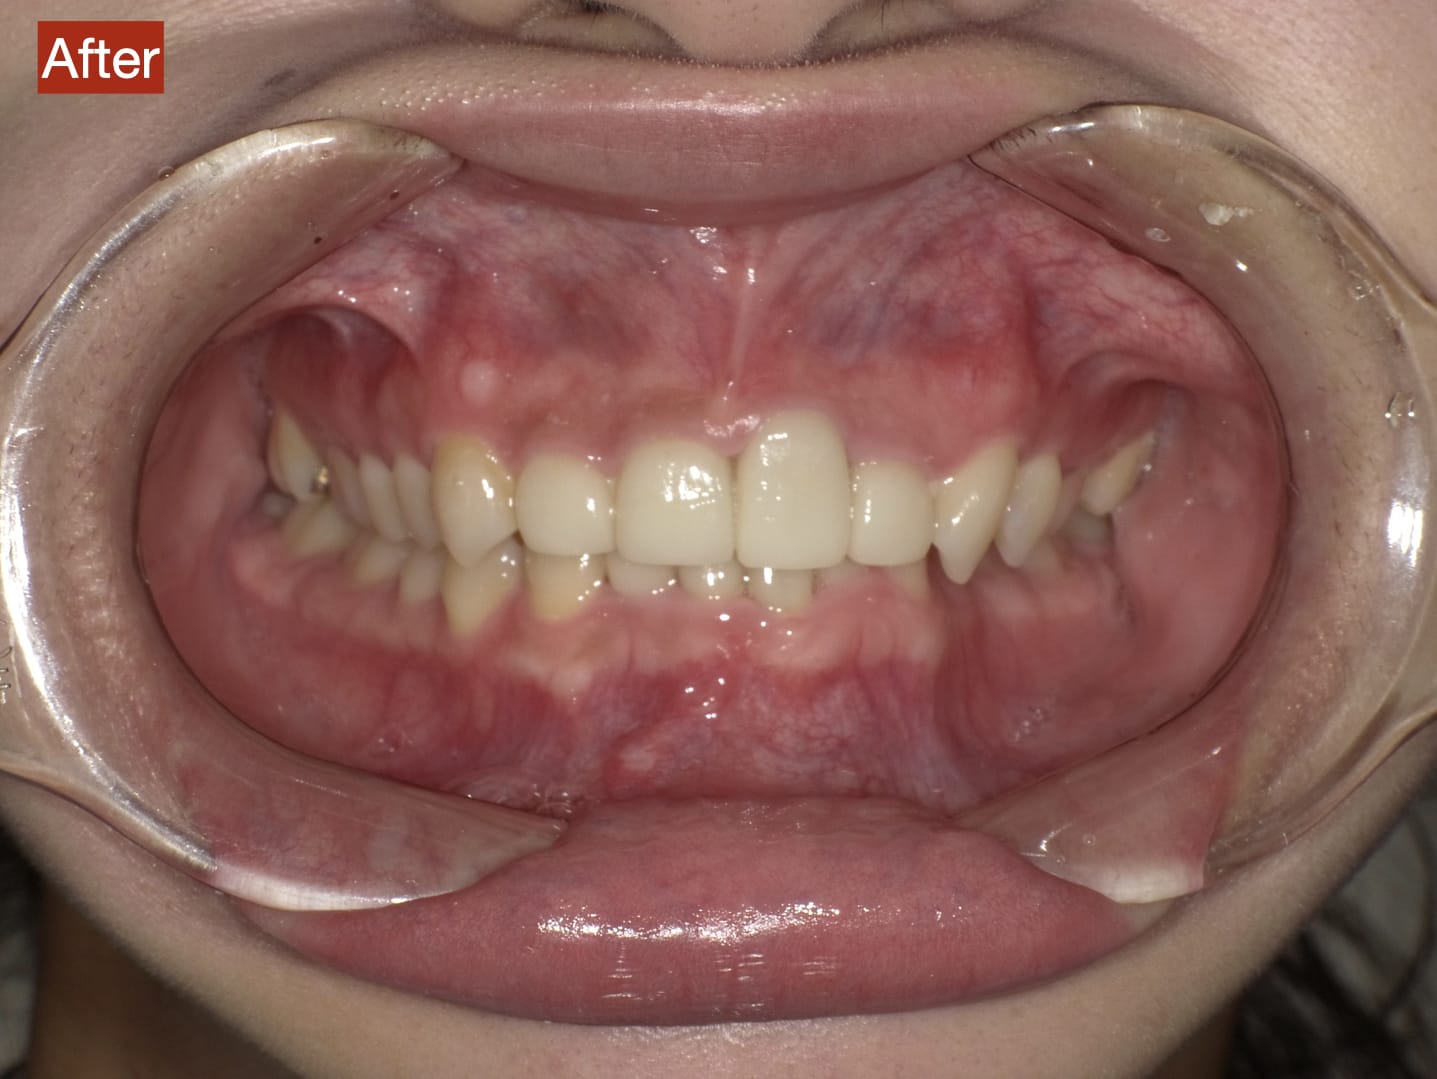

Case033

前歯が虫歯なのと、保険のプラスチックで大きく治療されていて色が悪いこと、歯並びが出っ歯気味であることを気にしてセラミックにしたいという主訴で来院された患者様です。

虫歯が大きかったところは神経治療をきちんと行い、

初診時を含めてトータル4回のご来院で完了です。

今回は前歯を下げる、歯列を整える、白すぎず自然に綺麗に見える色というご希望に沿って治療しました。

ご興味のある方はいつでもご相談ください。

担当 理事長 佐藤 悠野